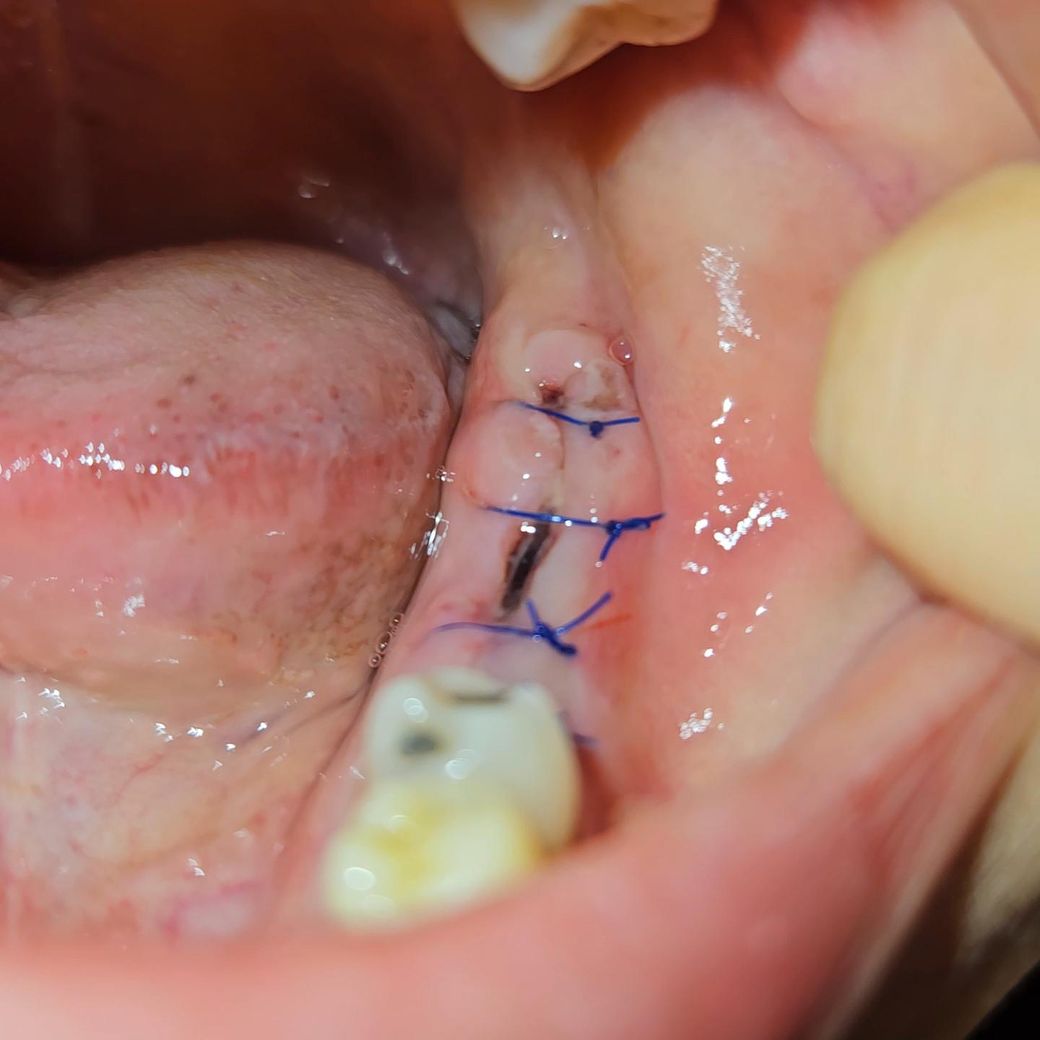

• 3번 째 사진

• 사진 보니 새살 올라 오는거 같기도 하고.. 염증같기도 하고...

사진상에 보이는건 잇몸이 치유되면서 생기는 자연스러운 현상이니 크게 걱정은 안하셔도 될것같습니다.

5월 20일 임플란트 심은 것은 정상적으로 아물고 있는 것으로 보입니다. 토요일 가 실밥 풀면 될 것으로 보입니다.

너무 불안해서 먼저 질문 글 드립니다 ㅠㅠ -> 사진으로 봤을때 염증의 양상은 아닙니다